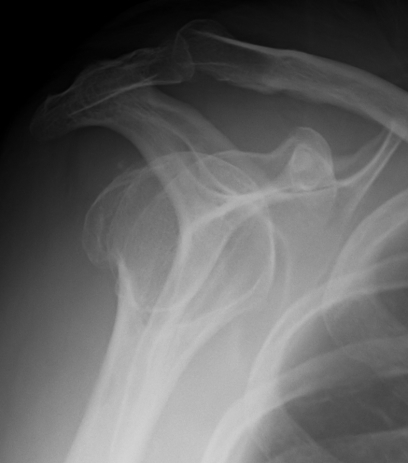

Xray / CT

Deforming force - rotator cuff displaces superiorly (supraspinatus) and posteriorly (infraspinatus)

Look for occult surgical neck of humerus fractures